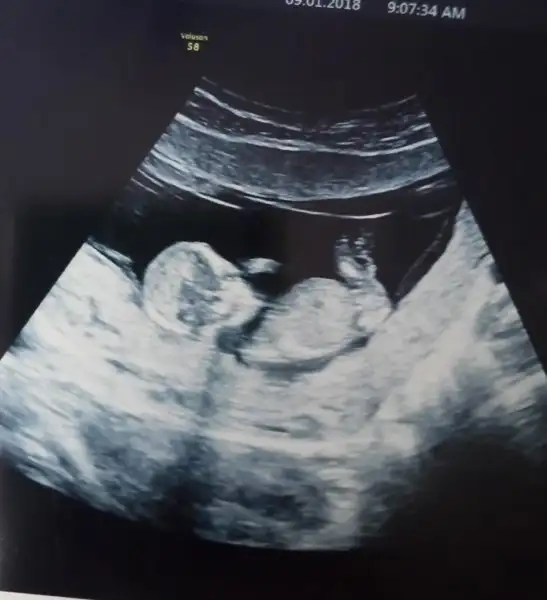

ben baska arkadasa ultrason goruntusunden genital nub tahmini yapmistim tutmus. Ama bir turlu kendiminkini bilemiyorum ya nasil bir kisiligim var anlamadim gitti :KK45:

IMG-20180103-WA0001.webp bu ne sence 10 haftalik tam